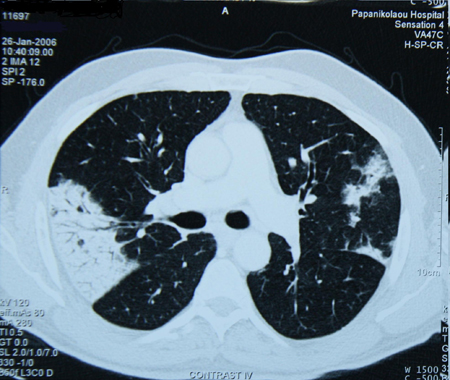

TC de alta resolução do tórax para procurar bronquiectasia (a qual nem sempre promove tosse produtiva), aspiração de corpo estranho, fibrose pulmonar ou outra doença pulmonar estrutural (que pode não aparecer bem na radiografia torácica). A doença pulmonar supurativa crônica é diagnosticada nos pacientes com sintomas clínicos de bronquiectasia, mas sem evidência radiográfica de bronquiectasia.[50] A TC também pode indicar a presença de um aneurisma aórtico ou um divertículo de Zenker. A expectativa quanto ao rendimento diagnóstico da TC do tórax em um paciente com tosse crônica e radiografia torácica normal é de que seja baixo.[3][Evidência C] Não há evidências de alta qualidade para apoiar o uso da TC de tórax na avaliação inicial dos pacientes com tosse crônica.[38]

[Figure caption and citation for the preceding image starts]: Tomografia computadorizada (TC) do tórax com presença de anel de sinete à esquerda em paciente com bronquiectasiaDo acervo pessoal da Dra. S.M. Bhorade, University of Chicago Medical Center [Citation ends].

[Figure caption and citation for the preceding image starts]: Tomografia computadorizada (TC) do tórax com vias aéreas dilatadas e espessadas e um padrão de árvore em brotamento periférico em paciente com bronquiectasiaDo acervo pessoal da Dra. S.M. Bhorade, University of Chicago Medical Center; usado com permissão [Citation ends].